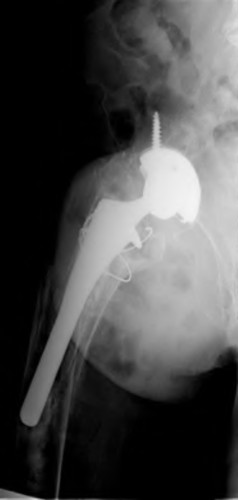

A 72-year-old male presents 2 years status post fixation of an impending pathologic right femur fracture due to metastatic renal cell carcinoma. He is minimally ambulatory due to pain. Despite radiation therapy, there has been progression of the lesion with extensive cortical bone loss, which is shown in Figure A. A proximal femoral replacement arthroplasty is performed without complications, and is demonstrated in Figure B. Which of the following is true regarding this patients post-operative course?

Deep prosthetic infection is the most common complication after hip arthroplasty performed for salvage of failed internal fixation after pathologic proximal femoral fracture secondary to malignancy.

Jacofsky et al reviewed the complications in 42 patients with a mean age of 63 who were treated with hip arthroplasty for salvage of failed treatment of a pathologic proximal femoral fracture. Multiple different constructs were used.

The most common complication was deep prosthetic infection, which occurred in nearly 10% of the patients studied. All infections occured in patients whom had previously received radiation. The mean Harris Hip score improved from 42 to 83 points post-operatively, and 41 of the 42 patients were ambulatory at follow-up. Implant survivorship free of revision for any reason at 5 years was 90%, and free of revision for aseptic failure or radiographic failure was 97%.

Figure A shows a lytic lesion of the proximal femur with an intramedullary implant. Figure B shows a proximal femoral replacement.